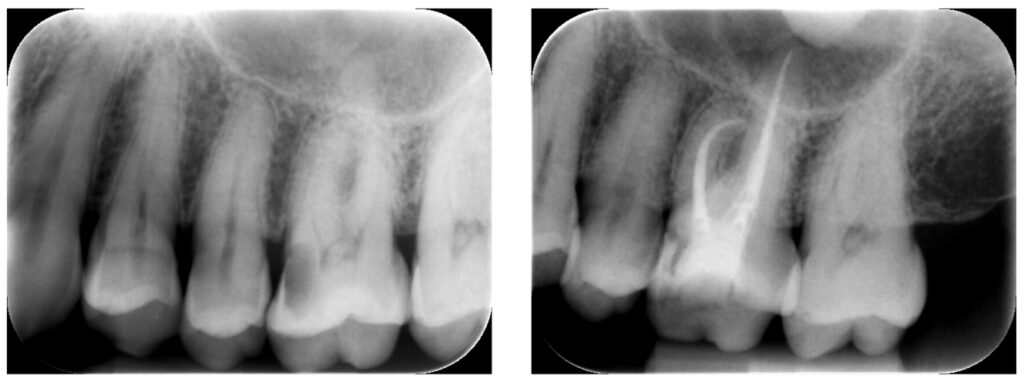

症例30:C3、症状無し歯髄炎

30代男性、他院で指摘されたカリエスを精密根管治療させていただきました。

根菅の再感染の防止を行いました。